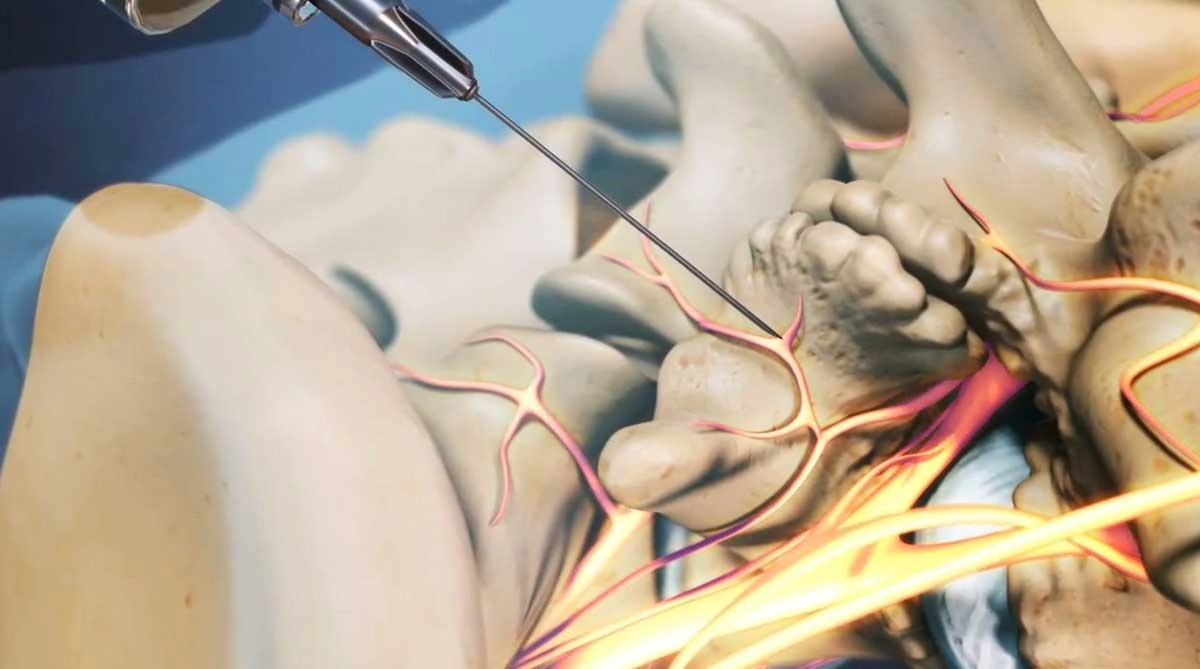

بلوک عصبی نوعی روش درمانی است که در آن ماده بیحسکننده و گاهی داروهای ضد التهاب مانند کورتون به نزدیکی عصبهای درگیر تزریق میشود تا التهاب و تحریک عصب کاهش یافته و درد تسکین پیدا کند. این روش میتواند به عنوان بخشی از درمانهای غیرجراحی دیسک کمر استفاده شود.

۱. بلوک ریشه عصبی (Epidural steroid injection): این روش شامل تزریق دارو به فضای اپیدورال در نزدیکی ریشه عصبی آسیبدیده است که شایعترین نوع بلوک برای دیسک کمر محسوب میشود.

نحوه انجام بلوک عصبی

انجام بلوک عصبی معمولاً تحت هدایت دستگاه فلوروسکوپی (رادیوگرافی زنده) یا سونوگرافی است. ابتدا ناحیه مورد نظر ضدعفونی شده و سپس سوزن به دقت در نزدیکی عصب یا فضای اپیدورال وارد میشود. پس از اطمینان از محل صحیح، دارو تزریق میگردد. کل فرآیند معمولاً کمتر از ۳۰ دقیقه طول میکشد و نیاز به بیهوشی عمومی ندارد.